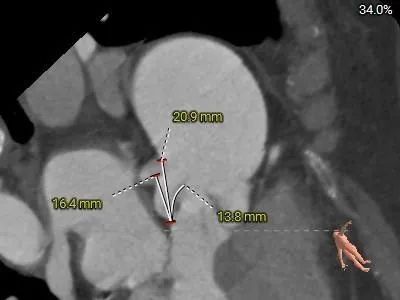

水平夹角测量:

虚拟瓣环与水平面夹角60°,横位心